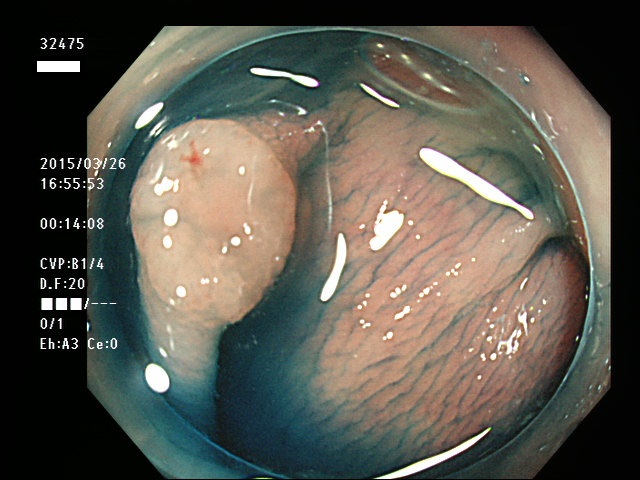

上記100名より抽出した平坦・陥凹型腺腫(=癌化の危険が高いが見落としやすい病変)の内視鏡写真